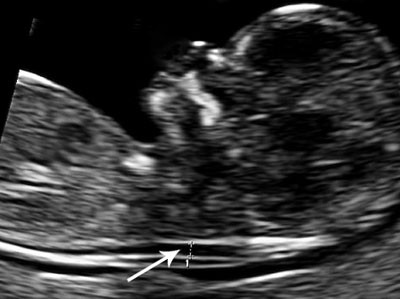

Figure 1:  Ultrasonographic image showing the location for measurement of nuchal translucency (NT) in the fetus. Photo: T. M…

Figure 1: Ultrasonographic image showing the location for measurement of nuchal translucency (NT) in the fetus. Photo: T. M. Eggebø

Prenatal diagnosis is regulated by the Biotechnology Act (1). Ultrasound with measurement of nuchal translucency (NT) and a combined ultrasound and blood test (CUB test) are considered as prenatal diagnosis. These are the indications for prenatal diagnosis as described in the leaflet Information to pregnant women on prenatal diagnosis (3).

Ultrasound during the 11th to13th weeks of gestation with measurement of nuchal translucency (NT) and a combined ultrasound and maternal blood test (CUB test) are considered prenatal diagnostic examinations. Increased NT is caused by an oedema in the fetal neck, and the blood samples taken from the mother measure the concentration of human chorionic gonadotropin (HCG) and pregnancy-associated plasma protein A (PAPP-A). The CUB test predicts the likelihood of an aneuploid fetus and fetal malformations (4) – (6), and the method was introduced to reduce risks associated with invasive procedures (7). Ultrasound as part of prenatal diagnosis can only be performed after prior genetic counselling. Ultrasound performed as part of regular antenatal care, i.e. the routine examination during the second trimester, and examinations due to medical indications are not considered prenatal diagnosis and not regulated by the Biotechnology Act (1, 2).

The fourth case history highlights the distinction between ultrasound as part of routine antenatal care and ultrasound as an element of prenatal diagnosis. If suspicion of an abnormality is raised by ultrasound in routine antenatal care, the woman should be referred. Increased NT is the most important marker for chromosome aberration, but measurement of NT is defined as prenatal diagnosis. According to the guidelines, a referral should therefore be based on an impression of increased NT, and not on an accurate measurement. Nevertheless 33 (52 %) of the private gynaecologists reported that they would make a referral only if their own measurement had revealed increased NT. The distinction between examinations based on medical indications on the one hand and prenatal diagnosis on the other is not uniformly practised. One reason might be that Norwegian doctors feel insecure about whether or not they are breaking the law by measuring the NT.